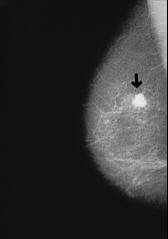

Brustkrebs und viele andere Krebsarten:

Blutgruppe A ist besonders anfällig für alle

A-ähnlichen Krebsarten.

The organism of blood group A is vulnerable for most kinds of cancer, for all kinds with cancer cells which are similar to body cells of type A. See: Cancer according to blood groups.

-- breast cancer, x-ray photo: http://www.prof-obwegeser.at/brustkrebs.htm